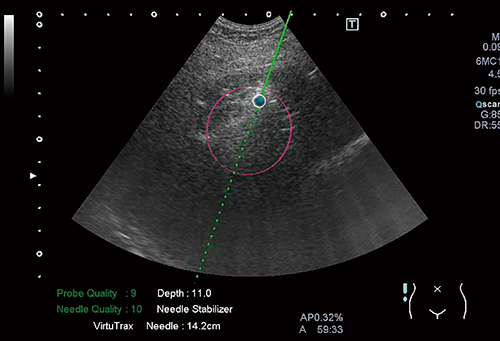

アジアで主流となっている超音波ガイド下インターベンションに使用する,東芝メディカルシステムズ社が開発中の“Needle navigation system”を紹介する。穿刺針の根元に磁気センサー(図12)を付け,針の先端の位置を画面上に●印で表示するシステムである(図13b)。針の先端の深さを確認し,目的の場所まで進めるためにはきわめて有用なシステムである。

図12 Needle navigation system

針の付け根に磁気センサーを装着することによって,針先位置を認識,表示する(a)。

磁気センサーを3本の針に装着し,プローブにも装着することによって,

超音波断層面と3本の針の三次元的な位置関係を認識,表示することができる(b)。

図13 Needle navigation system画像

針先の実像が見えなくても,針先位置が推定できる(青色の●印で示される)。